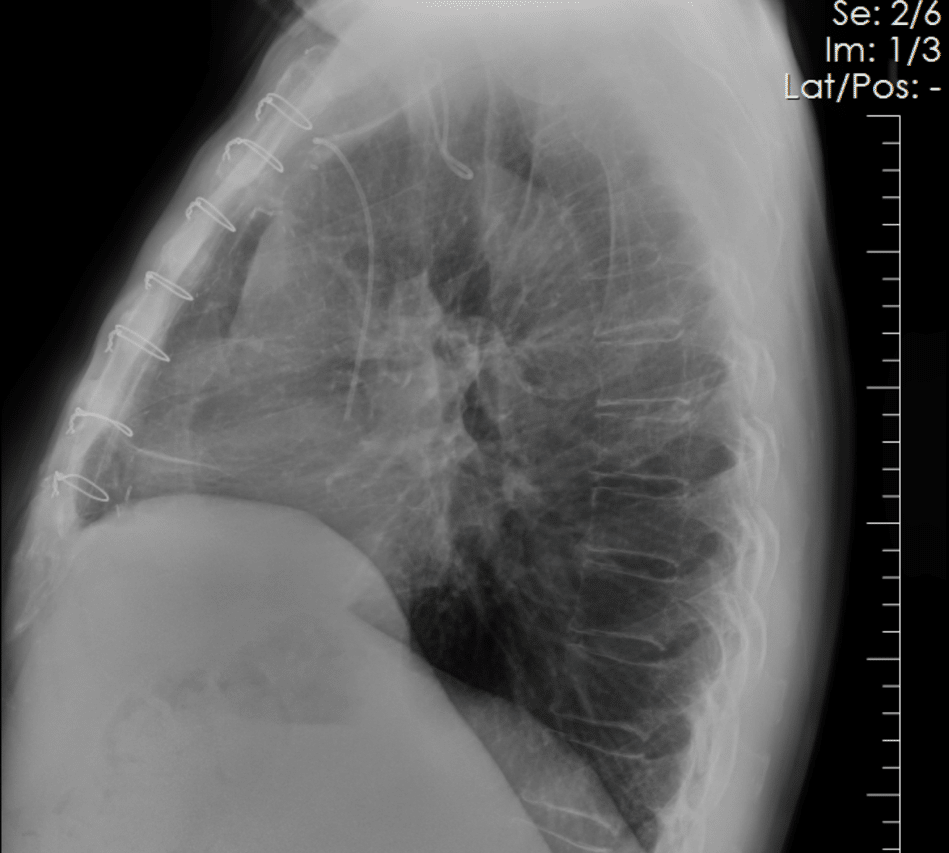

Coronary artery calcium becomes visible in the SpectralDR bone image and is confirmed on CT.

These images allow clinicians to separate overlapping structures and evaluate thoracic anatomy in different ways.

Soft-tissue images can reduce the visual impact of rib structures, while bone images highlight calcified structures within the thorax.

This separation may improve visualization of coronary artery calcium within routine chest radiography exams.